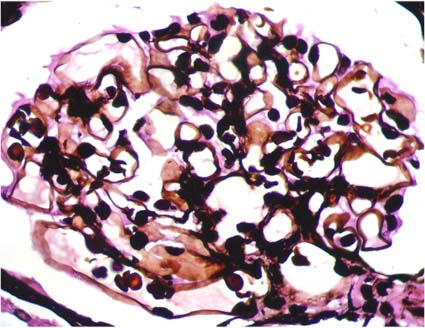

The mesangial matrix is formed by different types of collagen (III, IV, V and VI), microfibrillar proteins, glycoproteins, proteoglycans and other components (Venkatachalam MA, Kriz W. Anatomy (of the kidney). In Heptinstall's Pathology of the Kidney, Lippincott-Raven, Philadelphia, 1998, pp. 3-66) (Figure 4 and Figure 5).

Figure 4. The mesangial matrix, like the basement membranes of capillaries, Bowman’s capsule, and tubules are rich in type IV collagen, and has affinity by the methenamine-silver stain. See the irregular characteristic aspect of mesangial matrix (in black) in a normal glomerulus (Methenamine-silver, X.400).